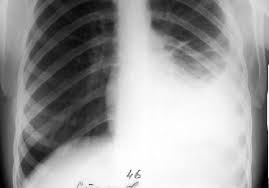

1. Рентгенография грудной клетки – на рентгеновском снимке отображается скопление фибрина в синусах плевры (при сухой форме заболевания) или наличие свободной жидкости (экссудативный плеврит на рентгене);